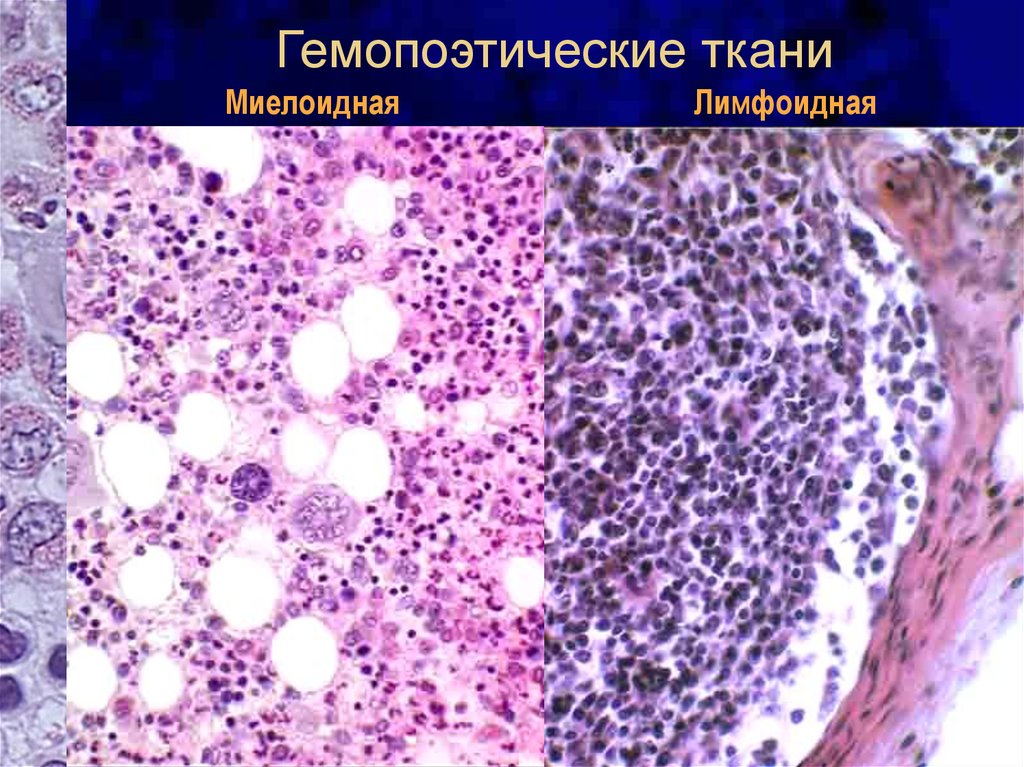

Изучение костного мозга: анатомия и функции